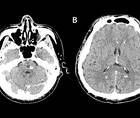

Ischemic Complications from a Facial Lipofilling Procedure